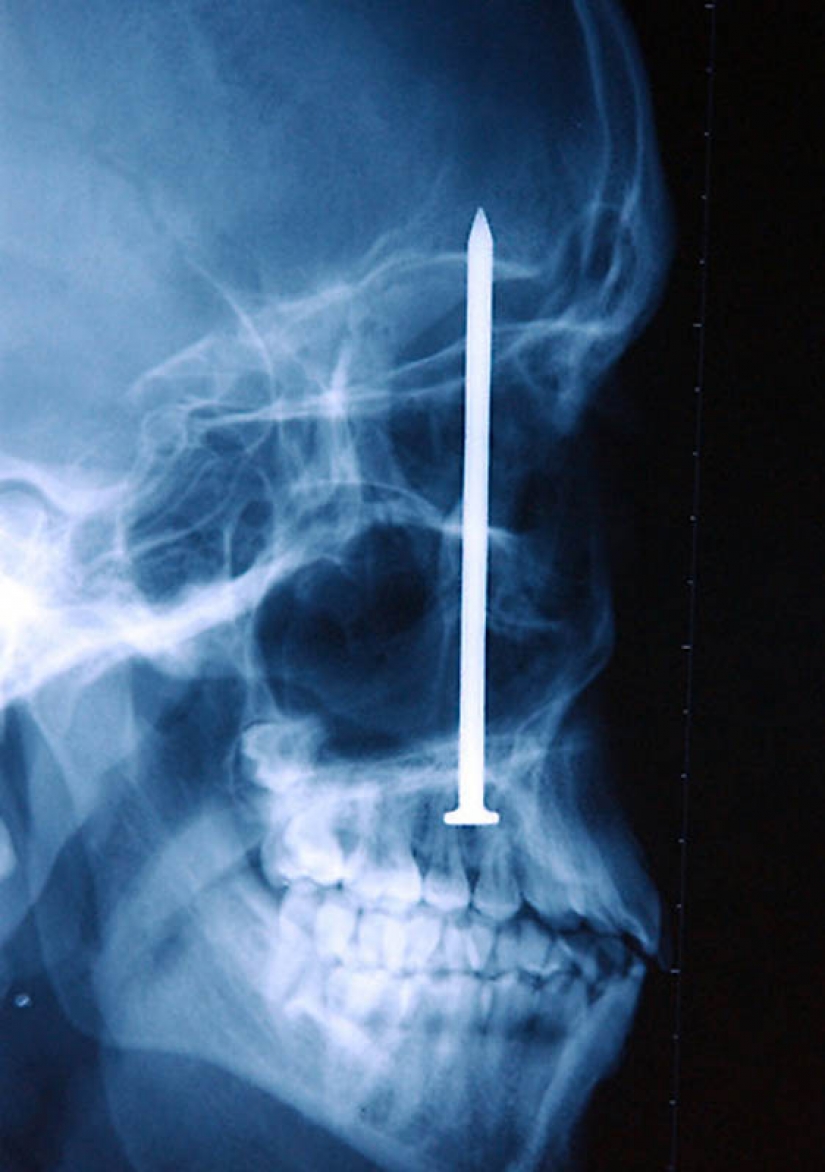

11. La lanza de la arpón, atrapados en la cabeza de un joven de 16 años de edad, niño de pesca.